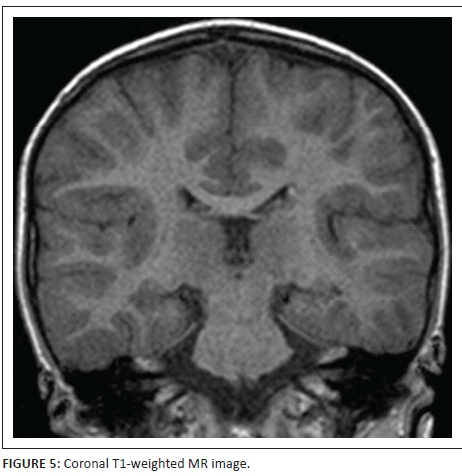

Figures 4 and 6 are coronal T1- inversion recovery sequence images and Figure 5 is a coronal T1-weighted image - all three confirming that the subependymal nodules are probably tubers. Also further delineating the cortical-subcortical hamartomas, left hippocampal signal abnormality and adjacent transmantle left temporal lobe band.